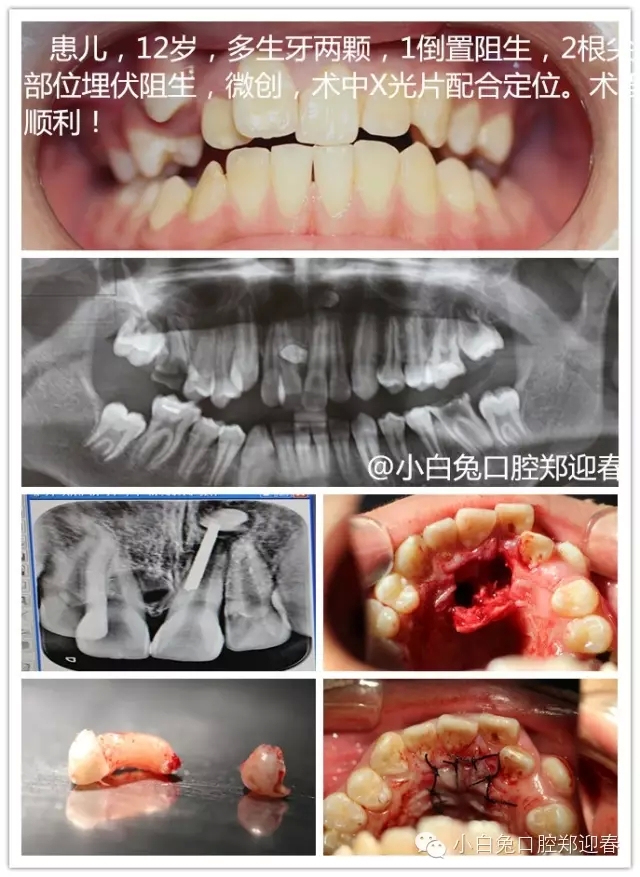

“多生牙”案例集錦(鄭穎春)......

額外牙可發(fā)生于乳牙列,也可發(fā)生于恒牙列,但恒牙列發(fā)生率多于乳牙列。額外牙經(jīng)常在上頜出現(xiàn),上、下頜出現(xiàn)比例為10∶1,可單個或多個、單側(cè)或雙側(cè)出現(xiàn),形態(tài)可同正常牙,也可是畸形牙、過小牙。